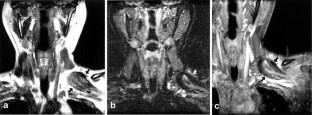

Fig. 1a–c